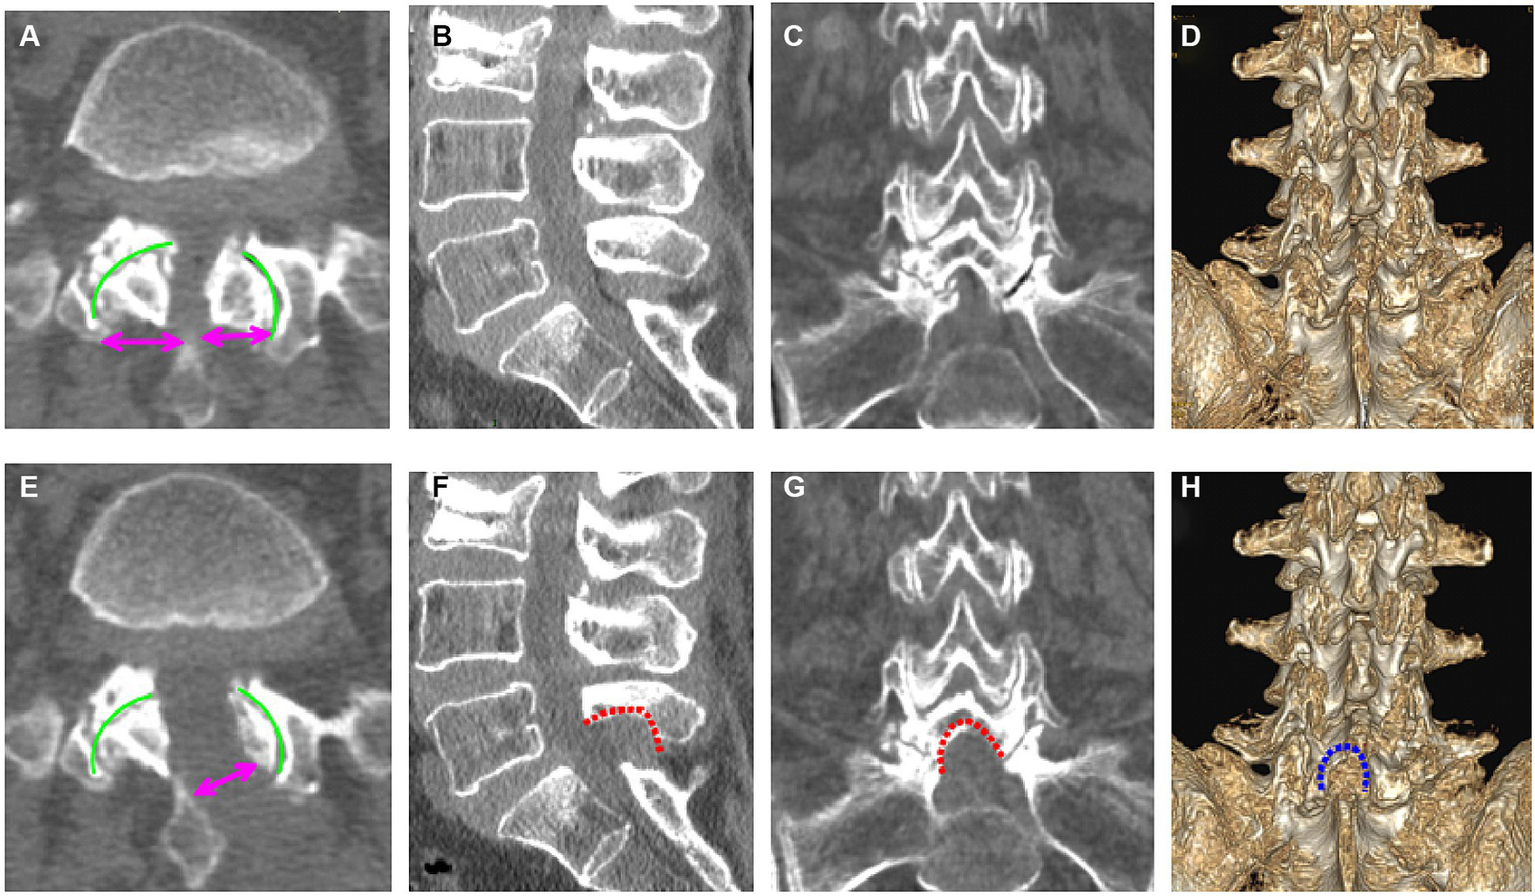

Figure 2

Pre- (A–D) and postoperative (E–H) computed tomography (CT) images of the lumbar spine (a 69-year-old woman). (A) Preoperative axial CT image of L5/S1; (B) preoperative sagittal CT image of L5/S1; (C) preoperative coronal CT image of L5/S1; (D) preoperative three-dimensional CT image of L5/S1; (E) postoperative axial CT image of L5/S1; (F) postoperative sagittal CT image of L5/S1; (G) postoperative coronal CT image of L5/S1; (H) three-dimensional CT image of L5/S1.

Using the CareStream Pacs imaging system (OneX, Canada), two senior doctors measured the distance of the bilateral lamina from the spinous process root to the bilateral dorsal articular facet based on the CT image of the suprapedicular notch section as well as the width of the bilateral articular facet (Figures 2A,E). The transverse and sagittal diameters of the dural sac in the axial plane were measured via MRI (Figures 3A,C). All the indicators were measured twice, and the average value was calculated.

The radiological results are shown in Tables 1–3. Postoperative CT (Figures 2B–H) and MRI (Figures 3B–D) scanning demonstrated adequate decompression and no instability in all patients, and the contralateral lamina fenestration width was 9.23 ± 1.32 mm, which was less than the distance between the spinous process to the dorsal articular facet (13.46 ± 1.75 mm) (p < 0.001). The residual widths of the ipsilateral articular facet (15.92 ± 3.8 mm) and contralateral articular facet (15.18 ± 2.64 mm) were greater than 2/3 of their preoperative widths (12.13 ± 2.21 mm and 12.25 ± 2.8 mm, respectively) (both p < 0.001). The canal area significantly increased from 8.29 ± 1.39 to 13.93 ± 1.82 mm (p < 0.001) in transverse diameter and from 9.27 ± 1.55 mm to 13.50 ± 2.40 mm in sagittal diameter (p < 0.001).